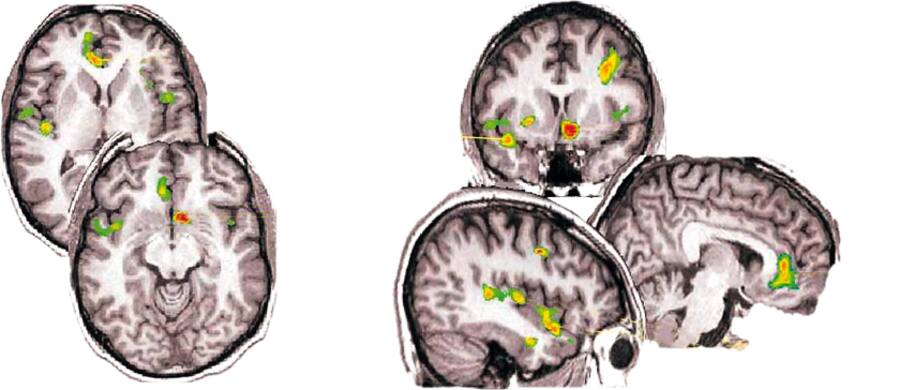

Diesen Umstand machte sich Placebo-Forscher Jon-Kar Zubieta von der University of Michigan zunutze. Er erzeugte bei 14 gesunden Freiwilligen Schmerzen, indem er ihnen eine Kochsalzlösung in die Kiefermuskeln injizierte. Dann verabreichte er eine Spritze mit angeblich schmerzlindernder Wirkung. Bald vermeldeten die Probanden ein Nachlassen ihrer Schmerzen. Gleichzeitig liessen die PET-Bilder erkennen, dass in bestimmten Regionen ihres Gehirns Endorphin-Bindungsstellen aktiviert wurden (siehe nachfolgende Grafik). Die hirneigene Schmerzabwehr war in Aktion getreten. «Dies versetzt der Idee, dass der Placebo-Effekt ein rein psychologisches statt physikalisches Phänomen sei, einen weiteren schweren Schlag. Die Verbindung zwischen Geist und Körper ist ziemlich klar», sagt Zubieta.

Mehr als nur psychologische Wirkung: Die Bilder oben zeigen Hirnareale während Schmerzerfahrung. Unten nach Verabreichung eines Placebos: Farbige Flächen zeigen Regionen, in denen das Gehirn selbständig schmerzunterdrückende Stoffe ausschüttete.

Quelle: University of Michigan